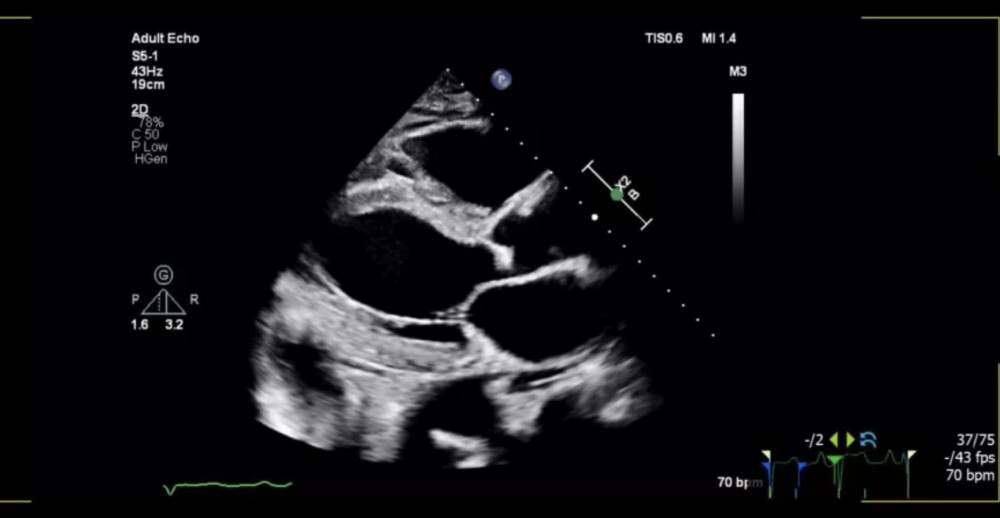

S5-1: Standart fazlı eko prob

S5-1X5-1 probları isə bütün xəstə növlərində, hətta texniki baxımdan çətin xəstələrdə belə, əla görüntü keyfiyyəti təmin edir.